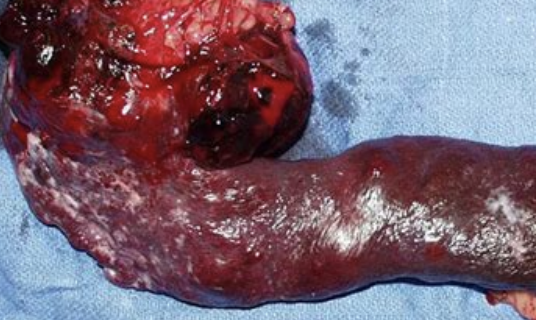

how is surgery used to treat hemangiosarcoma?

-stop bleeding

-total splenectomy recommended for diagnosis and palliative care

how common are splenic hemangiosarcomas in dogs?

make up 45-51% of canine splenic malignancies

8.7% chance of concurrent right atrial masses

what is the double 2/3s rule for splenic hemangiosarcoma?

2/3 of splenic masses are malignant

2/3 of those are hemangiosarcoma